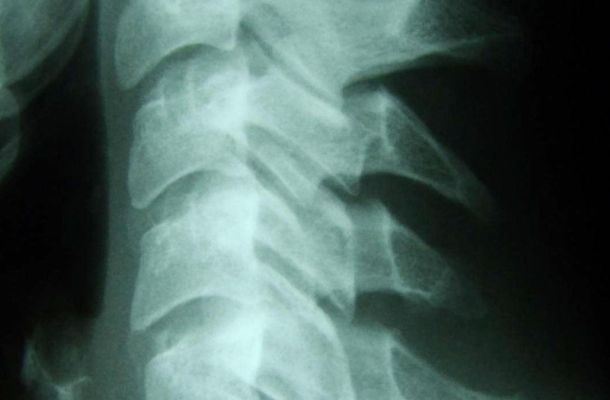

Vor jeder Behandlung steht die genaue Diagnose: Art und Ursache der Störung werden genau untersucht und Beschwerden ausgeschlossen, die nicht mit Chiropraktik behandelt werden können. Dazu werden auch weiterführende Abklärungen wie Röntgen oder Magnetresonanztomografie (MRI) durchgeführt.